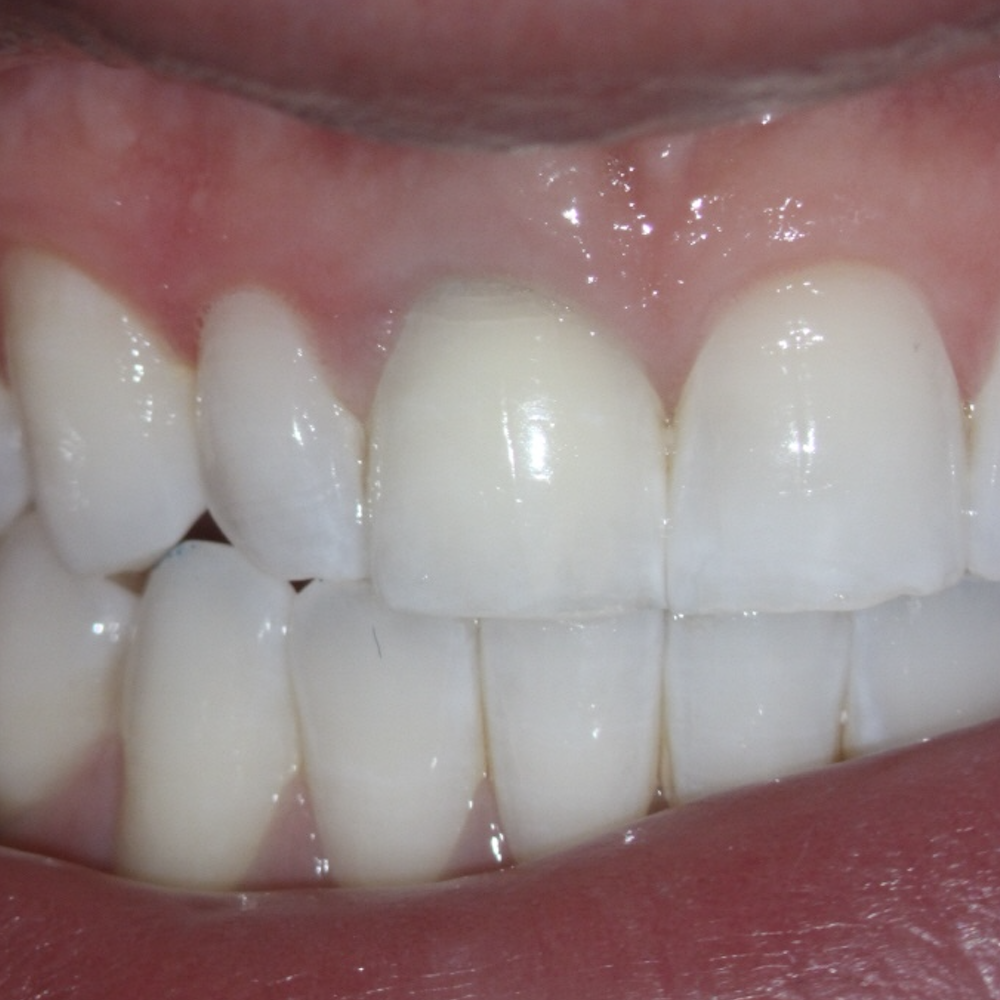

Resorption

Resorption is a condition where the tooth’s structure starts to break down, either from the inside out or from the outside in. It can be caused by trauma, inflammation, or other factors. Endodontic treatment for resorption involves removing the damaged tissue and reinforcing the tooth with materials that help prevent further damage. The aim is to save the tooth and maintain its functionality as much as possible.